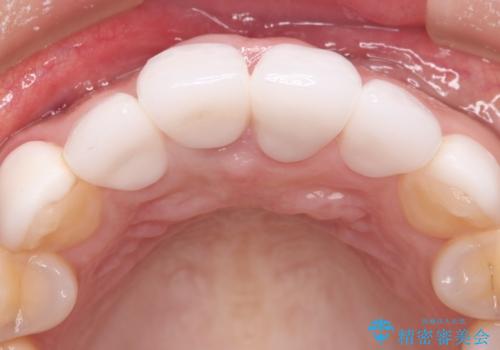

- 他院で治療した前歯の色が気になるということで来院された患者様です。前歯に色の差があり、レントゲンから内部にう蝕も見られたため、審美性に優れ、う蝕になりにくいオールセラミッククラウンで治療いたしました。

清掃性も上がったおかげで、歯肉の状態も良好に保てています。

色の調和もとれたので非常に満足いただけました。